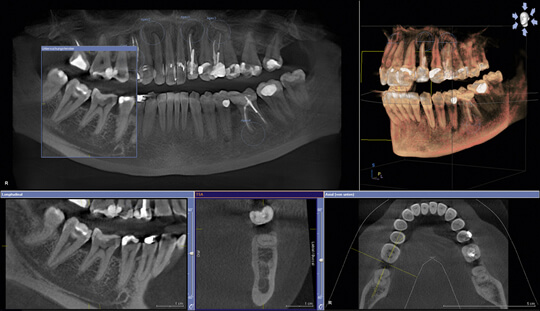

CT

インプラント治療、抜歯、歯周病、矯正治療など、精密な技術を要するものには、精密な検査が必要です。

三次元の立体画像を得られる歯科用CTにより、様々な方向から詳細な情報を得て、見えなかった部分を確認、診査することができるようになりました。

より正確で、より安全な診断を行うことが、治療の確実性を高めることにつながります。